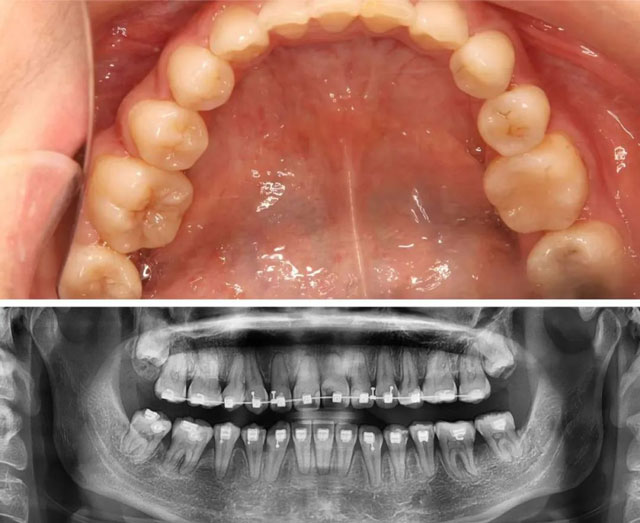

口内照片及全景片(2021年2月)

口内照片及全景片(2023年11月)